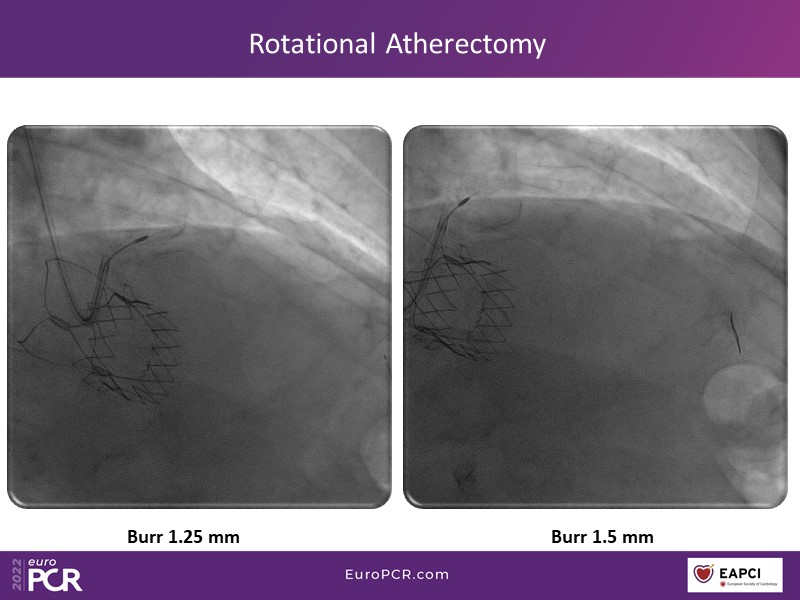

Alexandre Abizaid, Marco Valgimigli, Fazila Malik, Luca Testa, Patrick W. Serruys, Damiano Regazzoli, Kumar Prathap, and Sandeep Basavarajaiah take turns in this session to discuss two innovative technologies: a stent platform with nanotechnology and a novel drug-coated balloon (DCB). These novel technologies both have unique features that could change daily practice and improve outcomes.

- To find out more about the application and mechanism of a sirolimus coated balloon for coronary artery disease treatment with case presentations in complex settings

- To look at the technology behind the products, what the key data suggest and important takeaways from case permutations